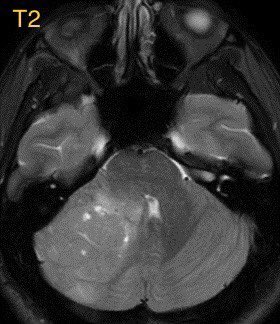

45 y/o M with no PMH presents w/ 1 month of persistent headaches followed by nausea & vomiting, what is the most likely diagnosis?

🔷Answer: Medulloblastoma, sonic hedgehog (SHH) activated

▶️Subgroup sonic hedgehog: ~30% of medulloblastomas

▶️Arise from granule cell precursors to FORM THE CEREBELLAR CORTEX (why SHH subgroup often looks cortically based in the cerebellum)

🔷Location: Most commonly LATERALLY IN THE CEREBELLAR HEMISPHERES (~62%)

🔷Imaging:

💡 Hypercellular tumor so DENSE on CT and DIFFUSION RESTRICTION (consistent feature)

▶️Round/lobulated morphology

▶️Hemorrhage is rare but calcifications seen in ~20%

💡 Most medulloblastomas enhance except group 4 which may have minimal to no enhancement